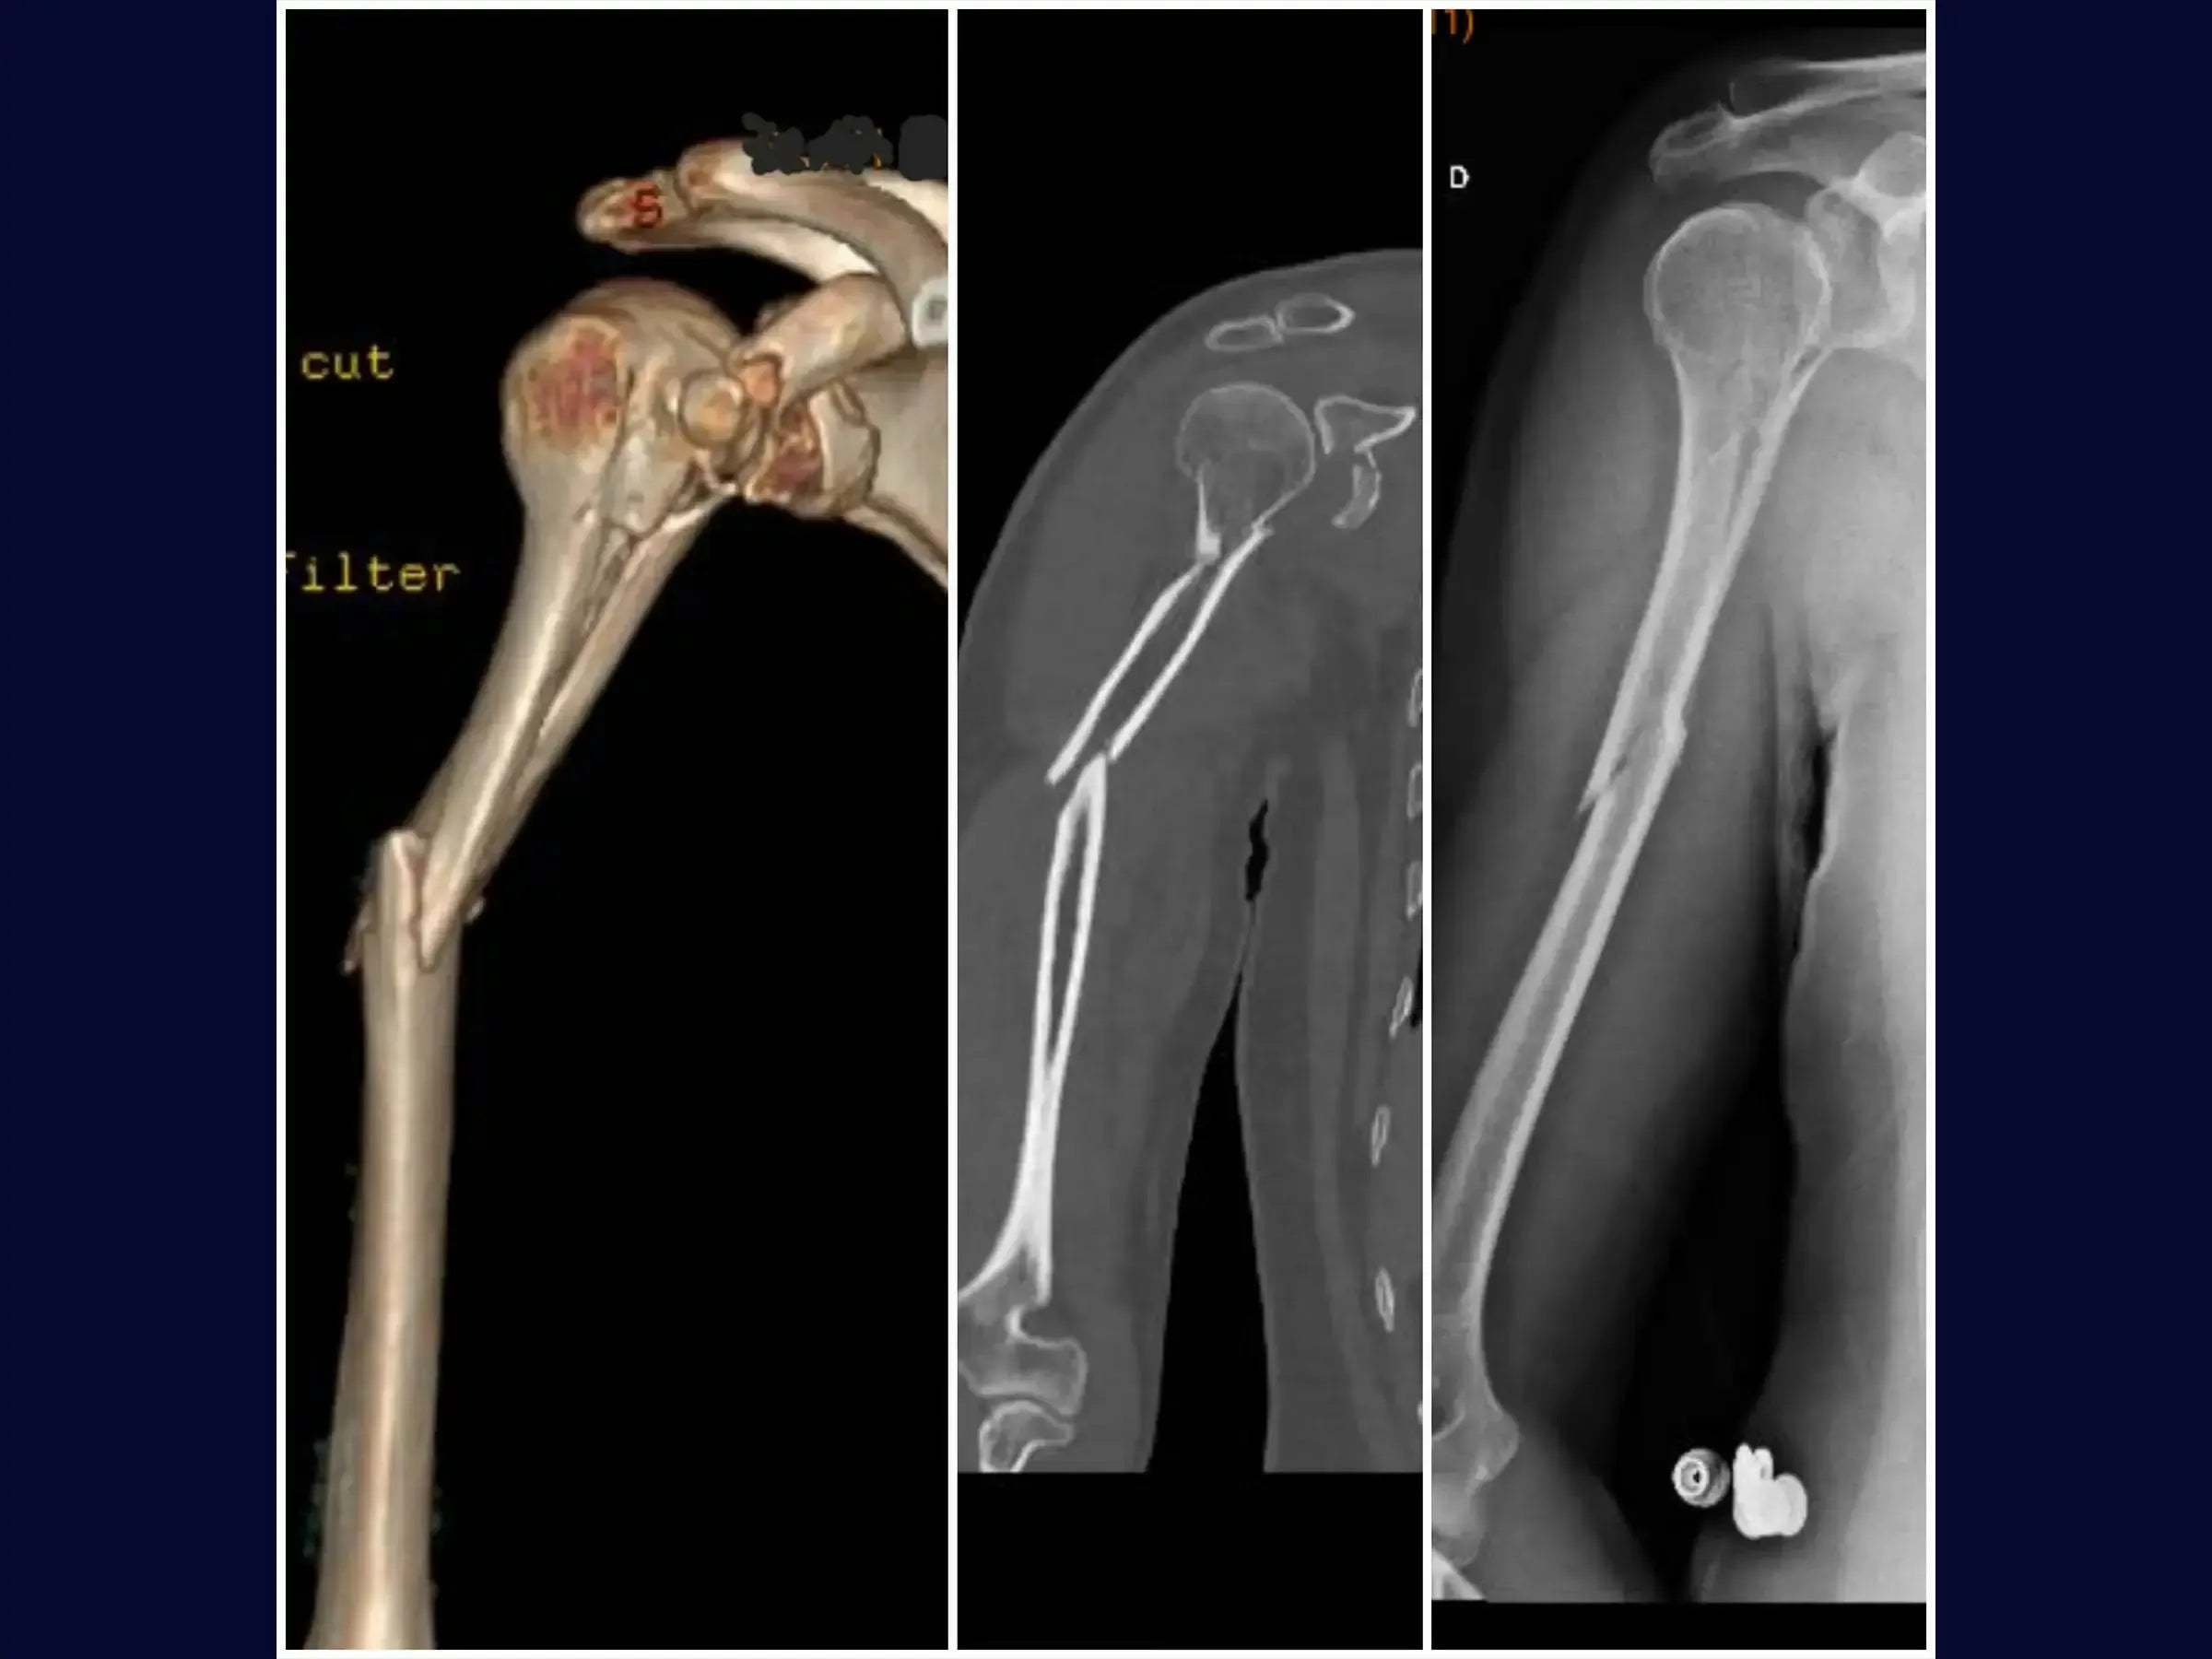

Fratura Segmentar do Úmero Associada a Fraturas da Glenoide e Processo Coracoide

Domine o tratamento de lesões complexas do ombro. Este treinamento oferece uma imersão técnica na abordagem de fraturas segmentares do úmero associadas a fraturas da glenoide e processo coracoide, através de um acesso deltopeitoral único.

- Manejo cirúrgico de fratura segmentar do úmero.

- Osteossíntese com haste intramedular e cerclagem no úmero.

- Reconstrução Segmentar do Úmero: Abordagem sistemática para identificação dos vértices da fratura, redução do segmento proximal e fixação com haste intramedular e parafusos proximais, complementada por cerclagem, para estabilidade e restauração anatômica.